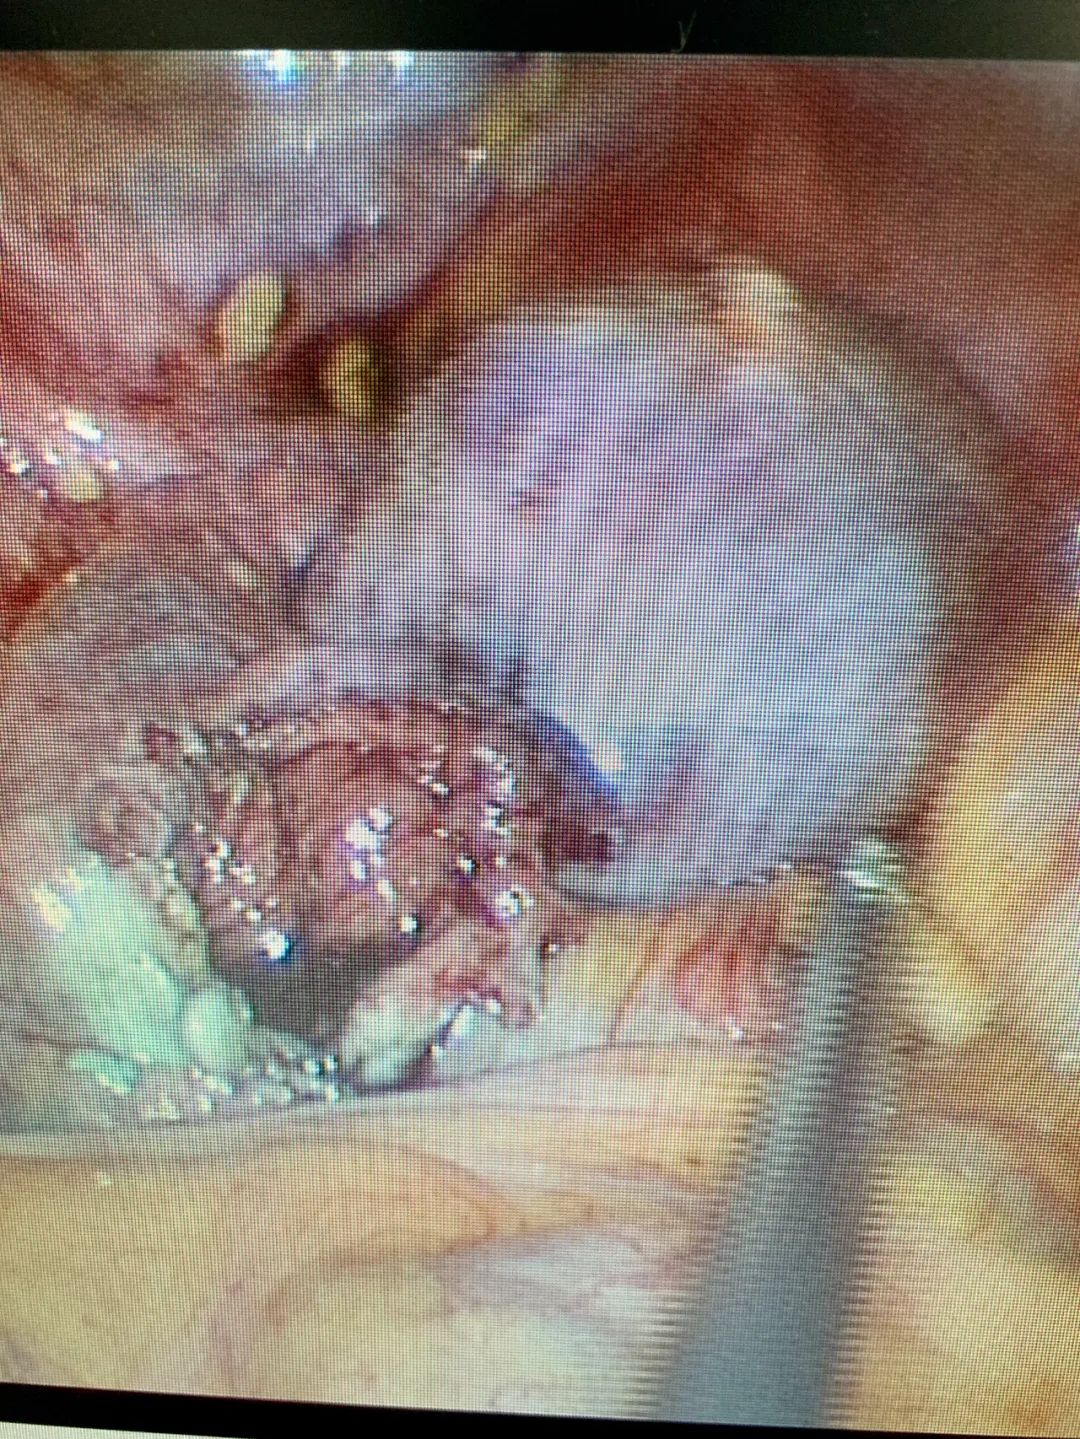

剪开末端组织,扩大切口,仅见少许伞粘膜。轻电凝末端浆膜层,使造口边缘外翻。双侧输卵管均疏通,成型良好。

LESS:双侧输卵管造口、疏通、成型